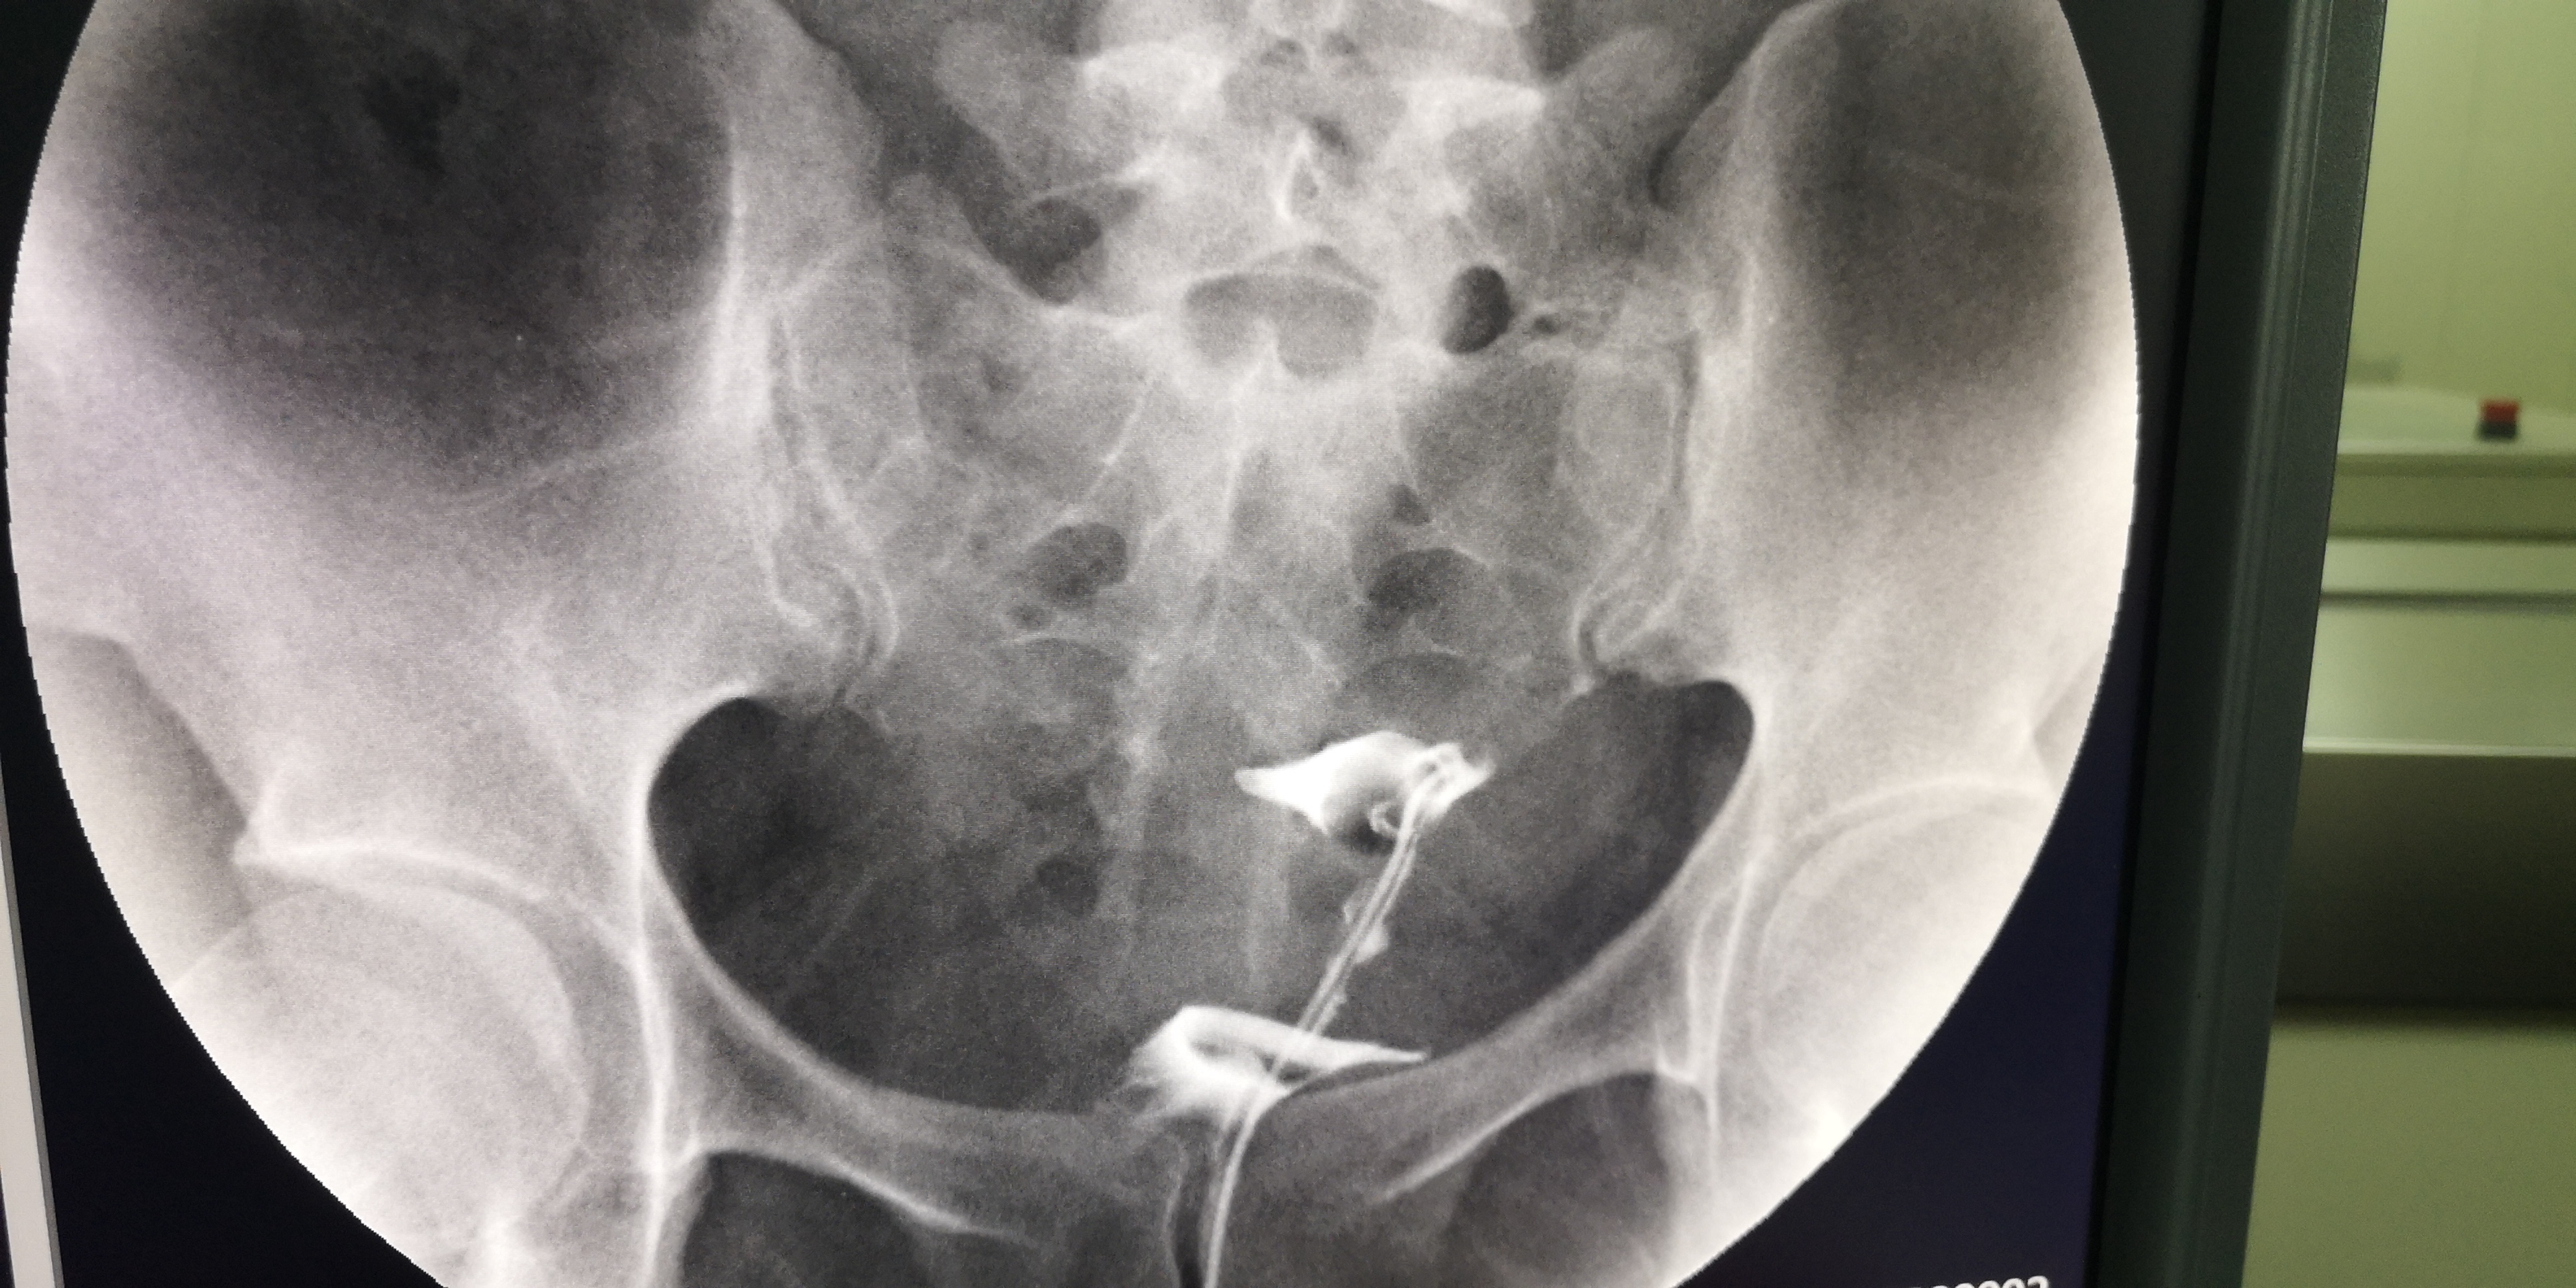

3月30日,我院妇产科成功开展了第一例子宫输卵管造影术。该手术由弋矶山医院生殖中心胡卫华主任专家团队的徐庆阳主任诊疗、余小英博士和我院妇产科医生共同完成。手术过程顺利,术中患者呼吸、心律平稳,无头晕胸闷、恶心呕吐等不适。术中清晰显示了患者子宫腔形态及输卵阻塞部位,从而明确了该不孕症患者的下一步治疗方向。

经X线的子宫输卵管造影术,是通过导管,向宫腔、及输卵管注入造影剂,利用X线诊断仪行X线透视及摄片,根据造影剂在子宫腔、输卵管、及盆腔内的显影情况,来了解输卵管是否通畅、阻塞部位及宫腔形态的一种检查方法。

子宫输卵管造影术损伤小,在有经验的医师操作下,并附以数字X光机的应用,能对输卵管堵塞作出正确诊断,准确率达80%,且具有一定的治疗作用。是用来了解输卵管是否通畅、通畅的程度及具体堵塞部位的最常用的检查方法。